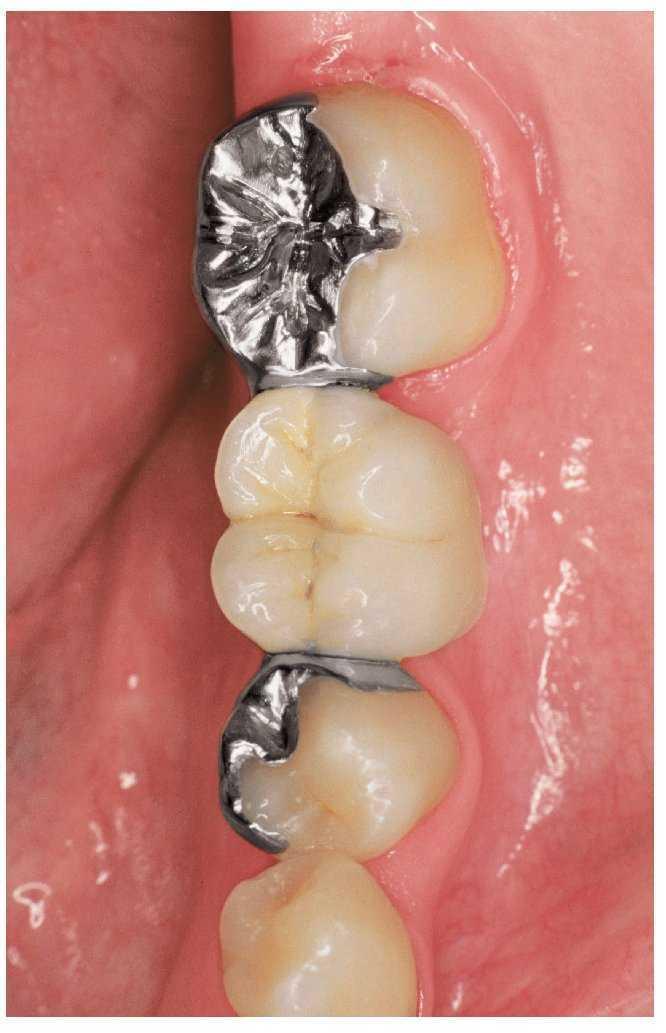

Figura 6a. Implante para sustituir al diente 36. Diente 35 sin caries y corona colada en el diente 37.

Figuras 6b y 6c. Implante unitario con pilar (b) y corona individual (c).